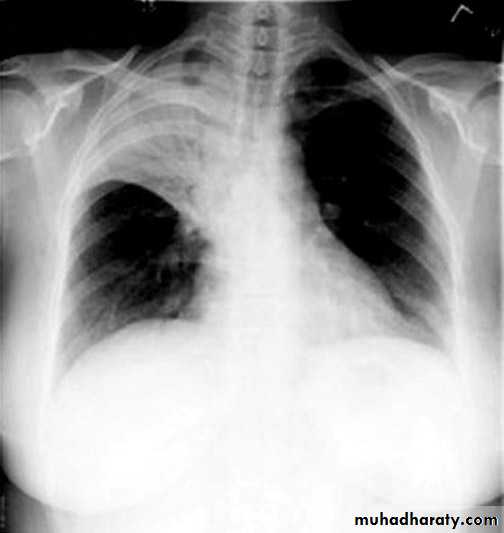

Pleural effusion ( free)